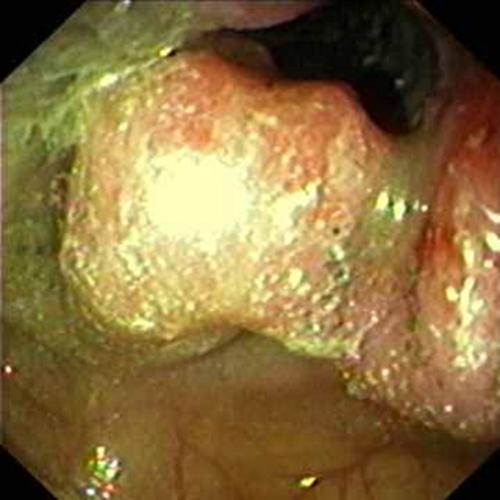

右半結腸癌粘液腺癌常見 臨床特點

右半結腸癌的粘液腺癌常見臨床特點